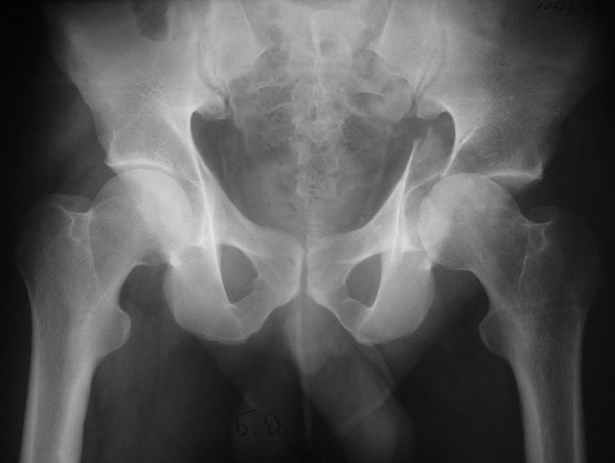

Re: Acetabular fracture

Высылаю пример еще одного случая, остеосинтез пластиной из подвздошного доступа.